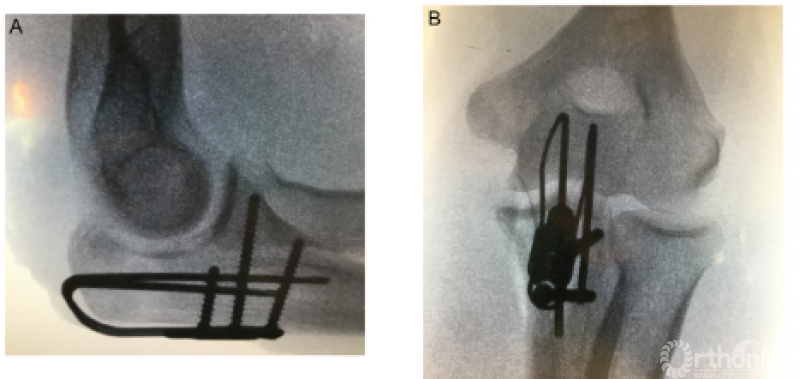

1、Lovy等采用鹰嘴雪橇板治疗Mayo II型鹰嘴骨折,在至少12个月的随访中,22例患者获得了满意的临床功能,均未取出内固定,也未出现感染或内固定相关的并发症,仅1例患者出现HO以及尺神经症状,做了关节镜下清理和尺神经前移。

7、Pasternack等提出了一种型的肘关节内固定架,只有10例患者(6例是三联征,2例新鲜肘关节脱位,1例陈旧肘关节脱位,1例外髁骨折),2016年获得FDA批准。平均术后74天后取出。内固定架能够减少外固定架带来的术后并发症,同时能够维持肘关节的稳定性,但由于初始损伤比较重,由于其他各种原因导致的二次手术率仍然较高。